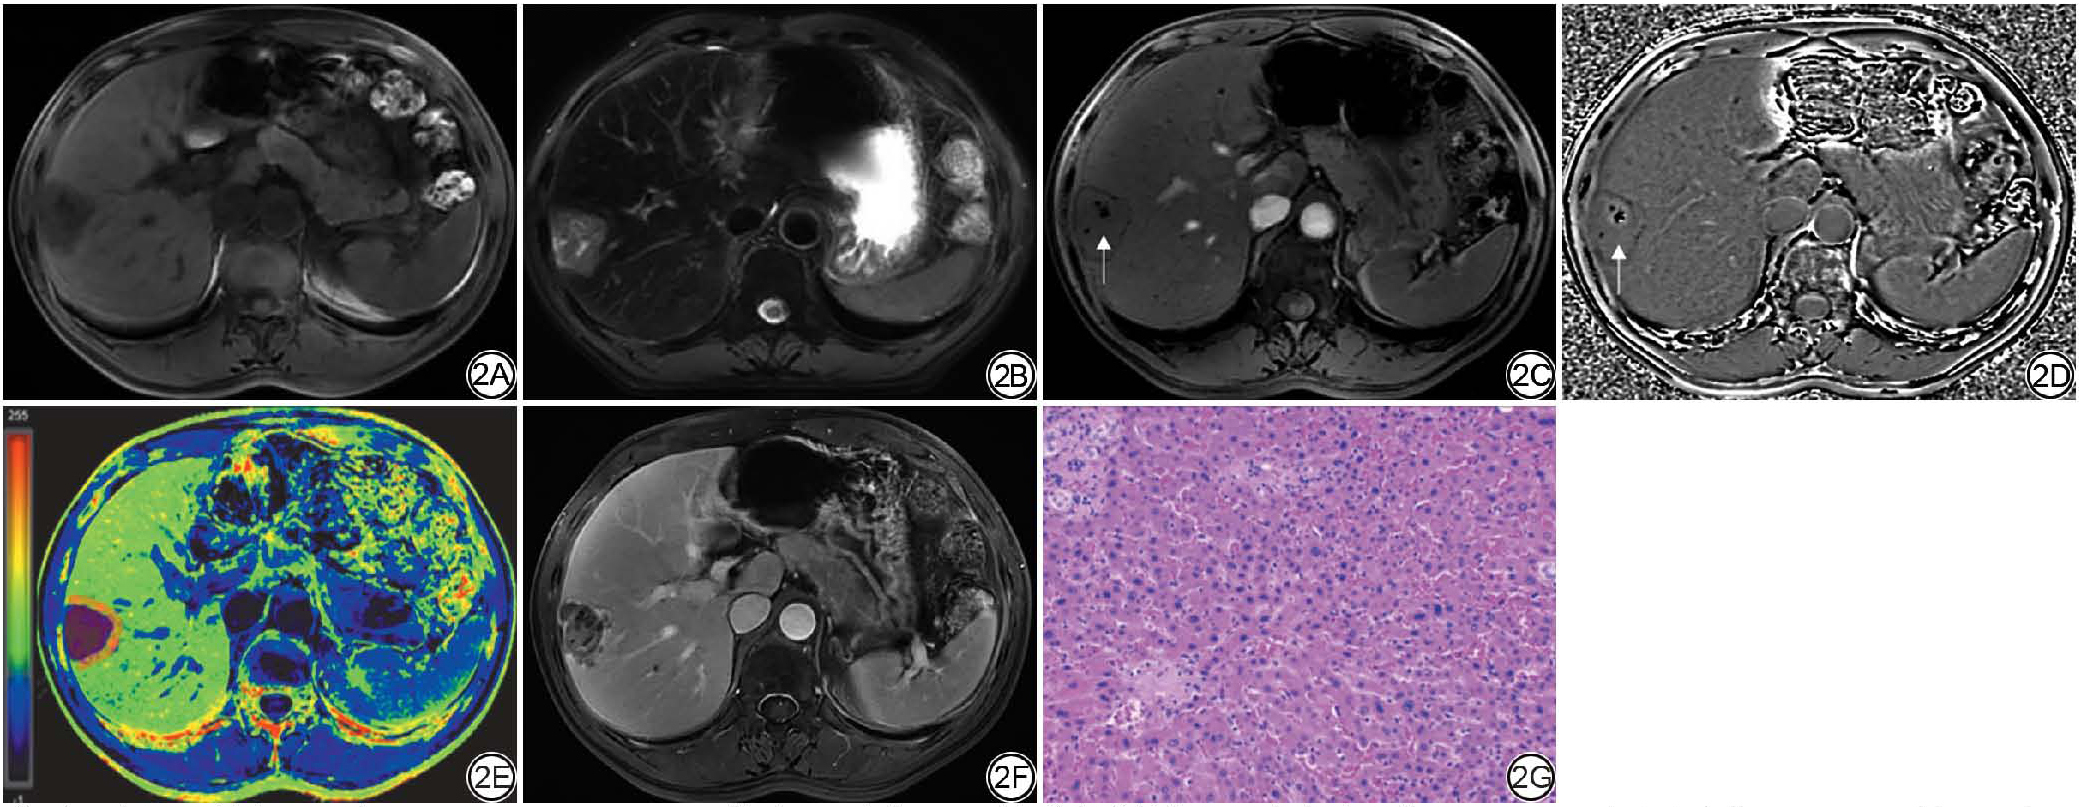

与MVI阴性组相比,MVI阳性组病灶ITSS分级更高,差异具有统计学意义(图1图2);两组之间病灶、瘤周R2*值差异无统计学意义,MVI阳性组△R2*高于MVI阴性组,差异具有统计学意义(表4)。

图2  女,54岁,病理证实为中分化肝细胞癌(HCC),微血管侵犯(MVI)分级M0级。2A~2B:分别为T1WI、T2WI图像,病灶未见明确出血,可见小囊变区;2C~2D:磁敏感加权成像(SWI)幅值图病灶内可见低信号点状出血(细箭),相位图呈低信号,肿瘤内磁敏感信号强度(ITSS)分级1级;2E:R2*伪彩图(蓝色至红色表示R2*值逐渐升高):病灶及瘤周5 mm区域感兴趣区(ROI)划定,△R2*=0.132;2F:Gd-EOB-DTPA增强MRI病灶可见不完整包膜结构;2G:组织病理学(HE ×200)证实为中分化HCC,MVI分级M0级。

Fig. 2  A 54-year-old female patient with pathologically confirmed moderately differentiated hepatocellular carcinoma (HCC), with microvascular invasion (MVI) grade M0. 2A-2B: T1WI and T2WI images, respectively, showing no clear blood products within the lesion; 2C-2D: susceptibility weighted imaging (SWI) magnitude image reveal hypointense punctate hemorrhages (thin arrow) within the lesion. The phase image exhibits low signal intensity, with an intratumoral susceptibility signal intensity (ITSS) grade of 2; 2E: R2* pseudo color image (the transition from blue to red indicates a gradual increase in R2* values): region of interest (ROI) delineation of lesion and 5 mm surrounding area, △R2* = 0.132; 2F: Gd-EOB-DTPA-enhanced MR shows an incomplete enhancing capsule; 1G: Histopathology (HE × 200) confirms moderately differentiated HCC with MVI grade M0.